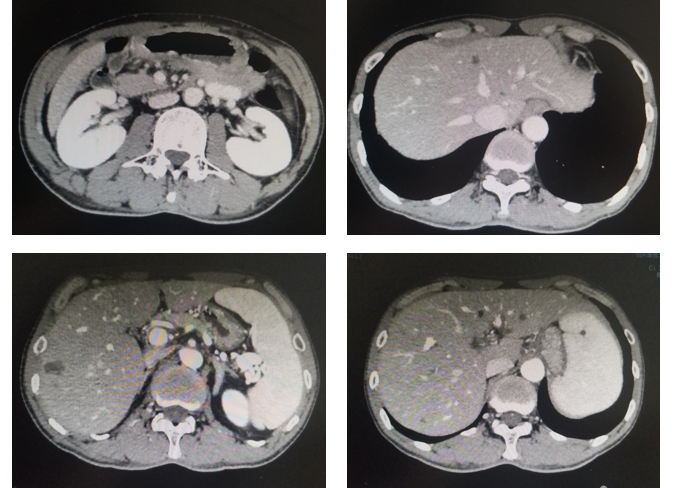

评估:治疗后3月和5月复查腹部CT情况(图2和图3).

图3. 腹部CT平扫+强化(治疗后2月,2020年1月)

图4. 腹部CT平扫+强化(治疗后5月,2020年3月)

影像科:根据患者治疗前、治疗后首次及再次复查CT看,原发病灶胃壁增厚明显减轻,肝转移病灶明显缩小,部分病灶消失,首次CT判效PR,再次复查CT确认PR。提示内科治疗有效。